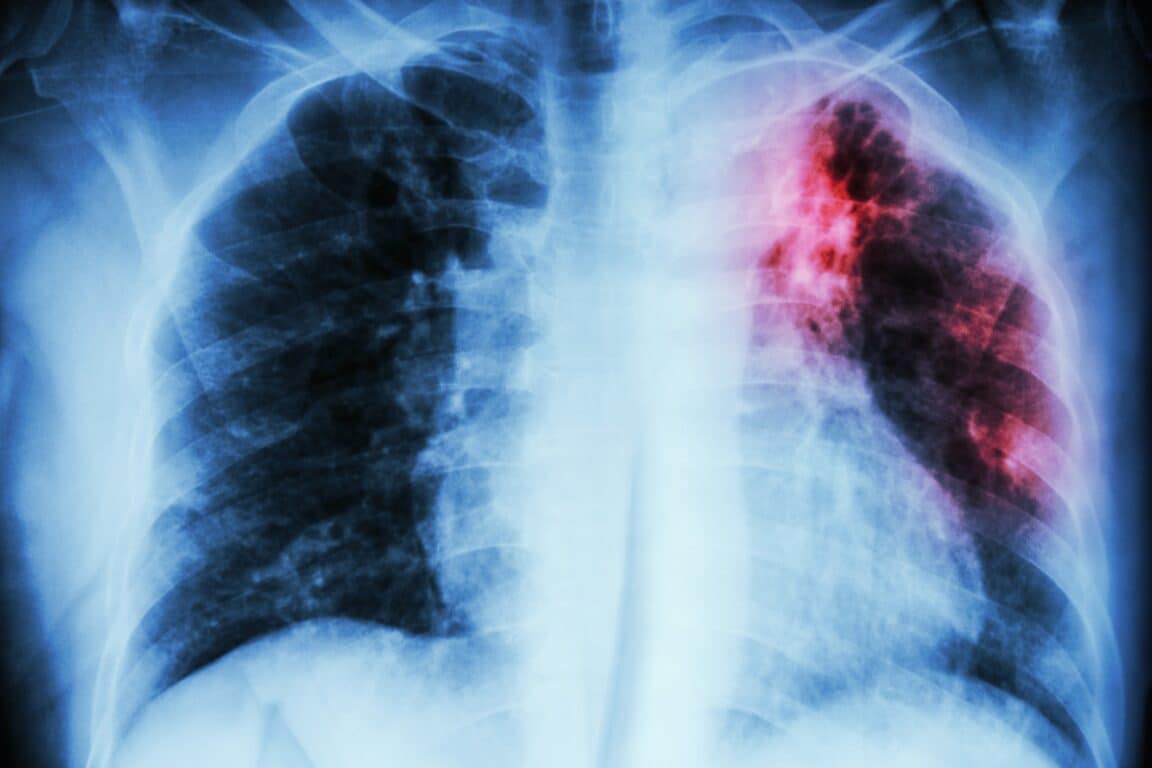

Cette affection bactérienne attaque principalement les poumons et se transmet par voie aérienne lors des éternuements, de la toux ou des crachats. Sa transmission est facilitée par la promiscuité et les conditions de vie précaires, ce qui explique sa persistance dans les régions défavorisées du globe. Contrairement aux virus émergents qui monopolisent l’attention médiatique, la tuberculose représente un ennemi ancien, connu et documenté, ce qui rend son bilan humain d’autant plus préoccupant.